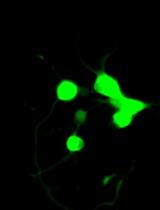

Fluorescence microscopy photos demonstrate that the colon epithelial cells uptake the NPs after 2h of incubation (Figure 6).

Figure 6. Fluorescence microscopy analysis of the cell uptake of the Dil-labeled nanoparticle. a) A representative fluorescence microscopy photo. b–d) Enlarged photo represents the nanoparticles internalized in the cytoplasm.